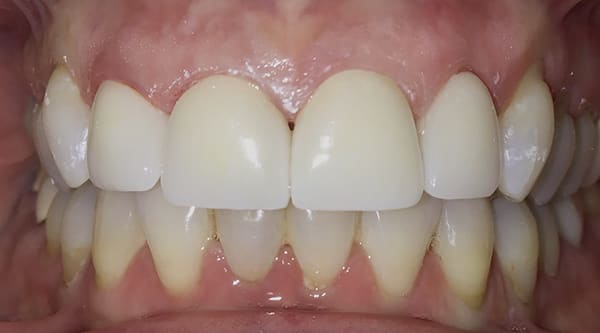

A female patient aged 57 years presented with altered passive eruption of the maxillary anterior teeth, which was diagnosed as a secondary condition to tooth erosion resulting from long-standing gastroesophageal reflux disease (GERD). Clear aligner therapy was initiated to level and align the occlusion and intrude the maxillary anterior teeth back to their original gingival position. After 18 months of poor patient compliance, improvement in tooth position was minimal and the amount of clinical overjet that was desired was not achieved. This limited the restorative armamentarium, and a decision was made to proceed with monolithic zirconia-oxide restorations. Following teeth preparation and tissue retraction, the case was impressed using an intraoral scanner (iTero® Element 2, Align Technology, Inc., itero.com). The final restorations were made of zirconium dioxide with a feldspar veneering ceramic shade 1M1 as the pressed layer on porcelain on the facials. The outcome of the case met the patient's primary concerns, achieving the lengthening and lightening of the anterior teeth that she desired. Because of the patient's continued challenges with GERD, however, she reported having difficulty with compliance related to the clear aligner therapy and whitening protocols, precluding a more ideal result. Nonetheless, the patient was pleased with her new smile and the clinician, given the challenging circumstances, was satisfied with the clinical results of the final restorations.